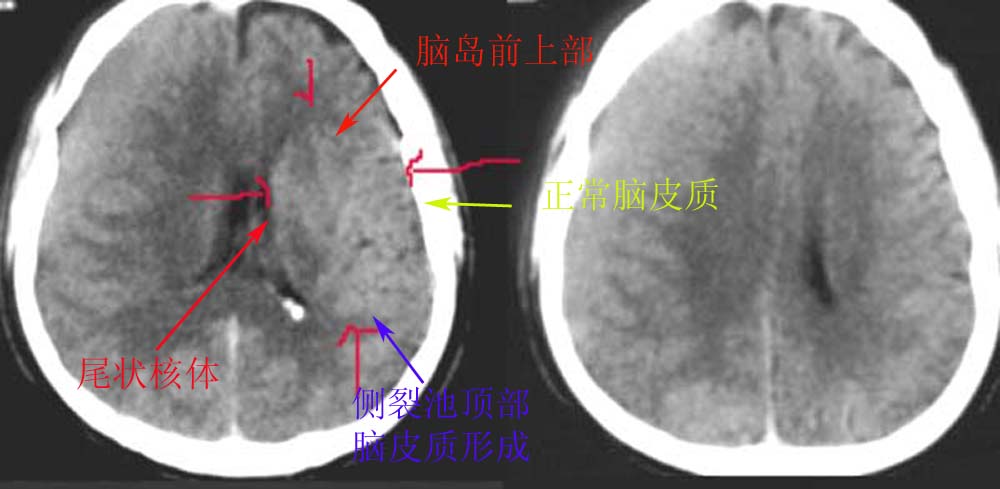

以下是引用dyqct在2006-11-13 14:57:00的发言:[br]我考虑为该病人位置不标准所形成,不知下面图示是否解释清楚。[br][br][br][br]